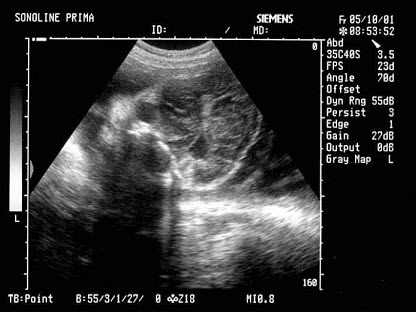

[单选题]女性,29岁,停经28周,产前超声检查如图,最可能的诊断为()A . 胎儿畸形,脑积水B . 胎儿畸形,腹壁裂C . 胎儿畸形,室间隔缺损D . 胎儿畸形,无脑儿E . 胎儿畸形,露脑畸形